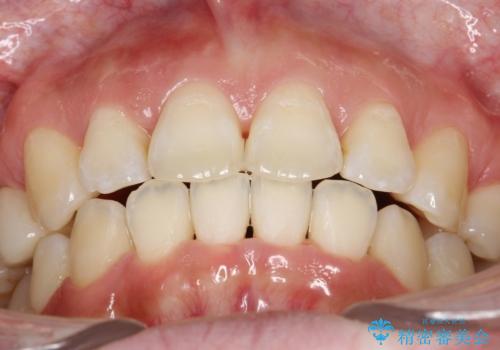

抜歯をして前歯を下げ、ガタつきを取り除く ワイヤー矯正

- 上顎両側第1小臼歯、下顎左側第2小臼歯の3本を抜歯、ラビアルのワイヤー矯正を計画した。

抜歯矯正は抜歯にできたスペースをつかい、前歯を積極的に下げたり、大きなガタつきを取り除くことができますが、その分時間がかかります。

ワイヤーを用いることで、矯正中に生じる様々な問題にその場で対処することができます。